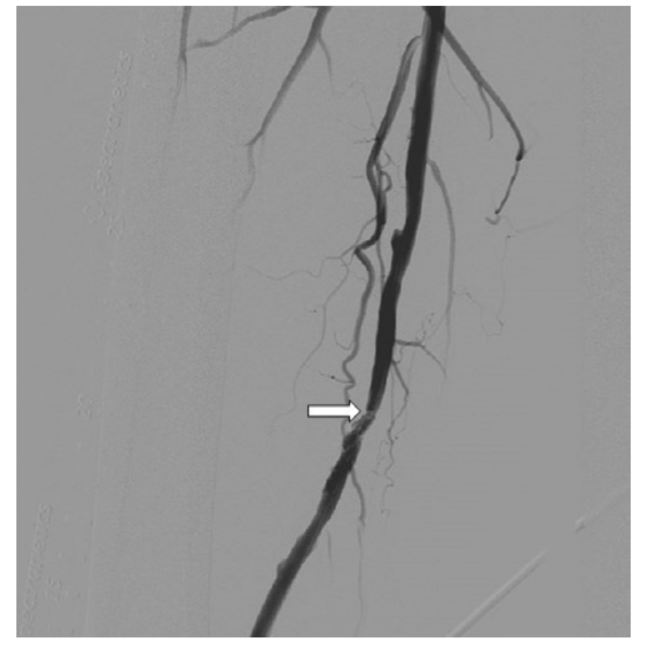

During the index procedure for the right lower extremity, an OmniFlush catheter (AngioDynamics) was positioned at the level of the right common femoral artery (CFA) for selective angiography with runoff (Figure 1). A Runthrough NS Extra Floppy guidewire (Terumo) was used to traverse the diseased segment. The Runthrough guidewire was exchanged for an .018-inch NiT-Vu guidewire (AngioDynamics) through a Glidecath support catheter (Terumo), and the lesion was prepared with a 5 × 80 mm Armada PTA balloon (Abbott Vascular). After vessel preparation, another balloon angioplasty was performed with a 6 × 120 mm Lutonix drug-coated balloon PTA catheter (BD). Angiography demonstrated less than 10% residual stenosis, but there were two grade D, flow-limiting dissections that were located in the mid-right SFA (Figure 2), disrupting an optimal hemodynamic result.